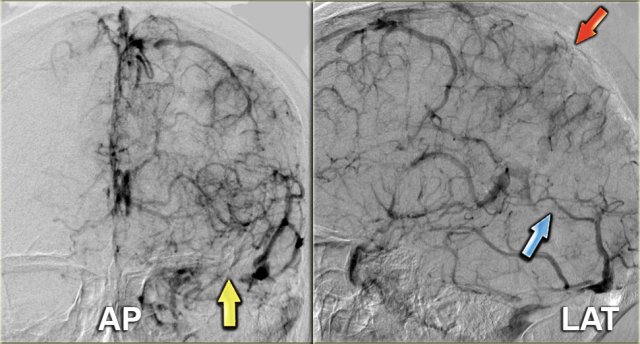

DSA

Angiography is only performed in severe cases, when an intervention is planned.

On the left images of a patient with venous thrombosis, who was unconsious and did not respond to anticoagulant therapy.

There is thrombosis of the superior sagittal sinus (red arrow), straight sinus (blue arrow) and transverse and sigmoid sinus (yellow arrow).

Continue with the video of the thrombectomy.

On the left a video of the thrombectomy.